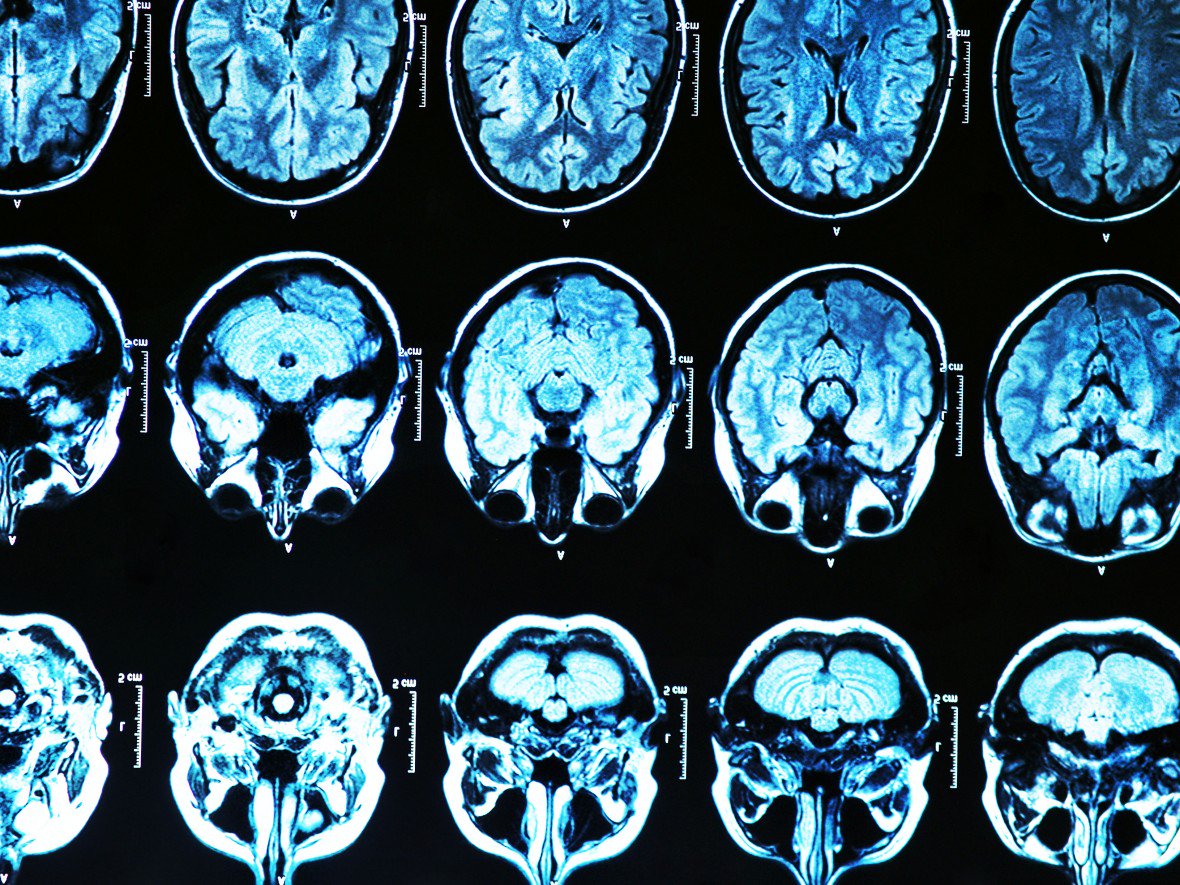

Salute Medici intendono testare una terapia genetica preventiva per l’Alzheimer Un innovativo trattamento contro la demenza inonderà il cervello dei pazienti con una…Antonio Regalado08/03/2019